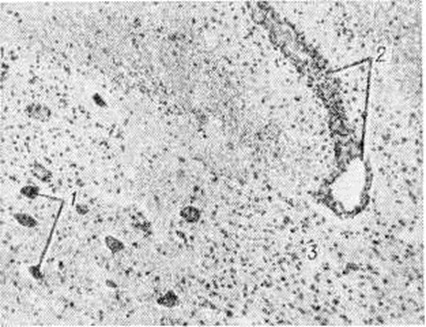

Рис. 2.

Микропрепарат спинного мозга при миелополирадикулоневрите: воспалительная реакция в белом и сером веществе спинного мозга; нервные клетки (1) в состоянии пикноза и дистрофии; перивенозная инфильтрация лимфоцитами (2); диффузно-очаговая пролиферация глии (5); окраска пикрофуксином.